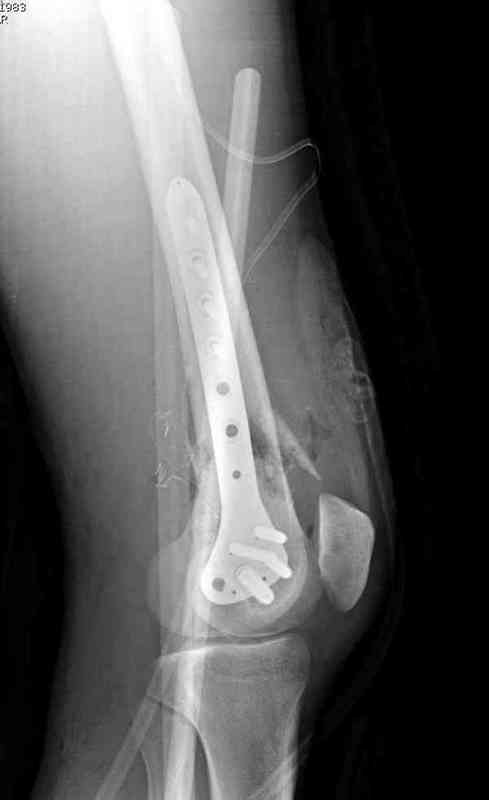

Вчера утром поступил больной с огнестрельной раной, осмотрен сосудистым специалистом, сделана ангиограмма (снимки) Во время операции при вскрытии обнаружили кровотечение, рану забили салфетками, установили пластину locking DePuy.

Из-за возрастающего давления в компартменте сделана фасциотомия и вызванный сосудистый хирург ушил разрыв вены на уровне перелома. Все раны оставлены открытими, в пятницу закроем.